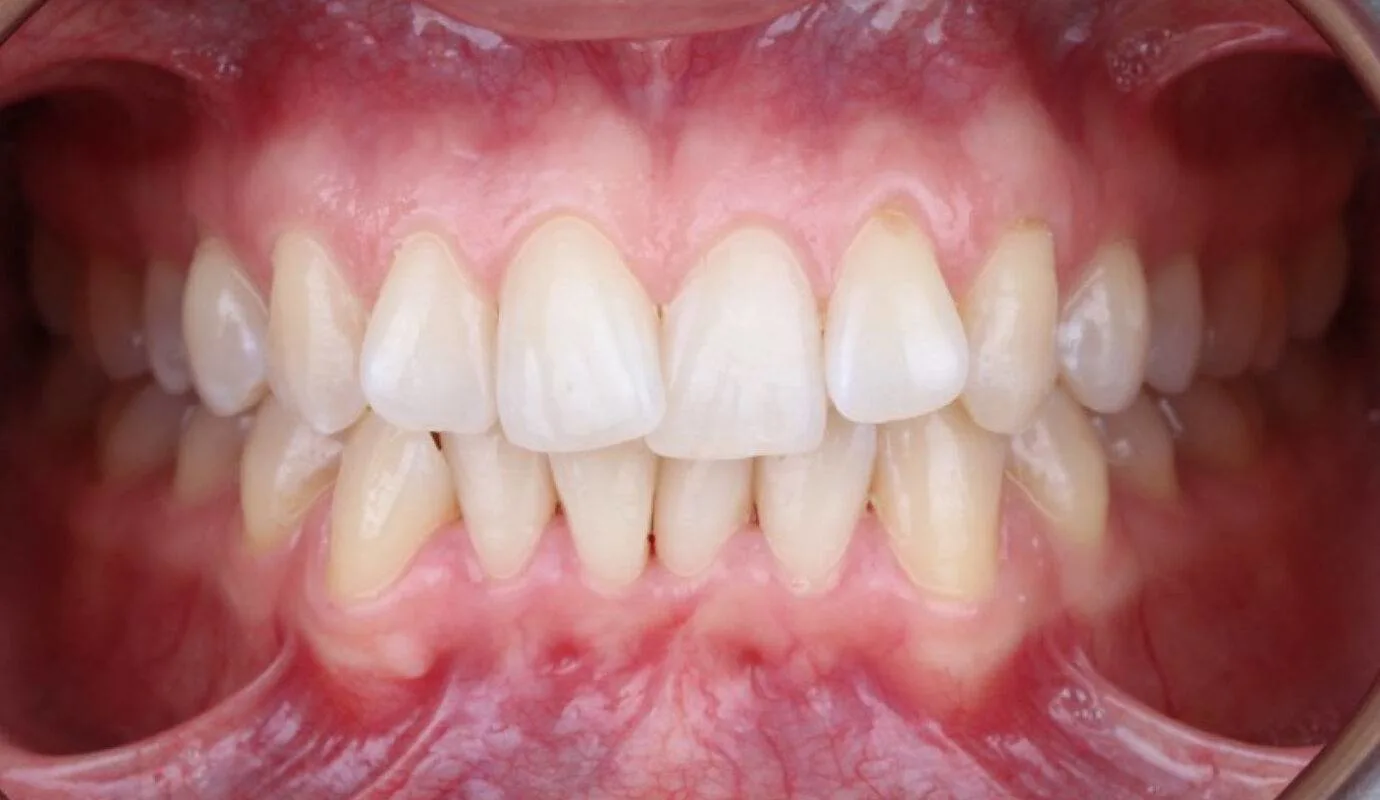

Before & After Invisalign® Gallery